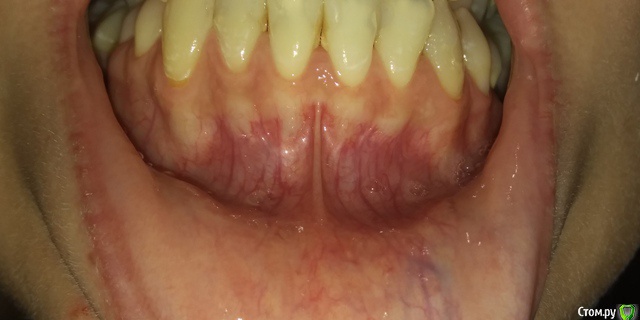

Есть рецессии на нижних зубах и на верхнем клыке слева и резорбция. Ортодонты говорят, что это последствия неправильного прикуса, травмирующего смыкания и с брекетами все стабилизируется, но из-за движения зубов может и усугубиться, как повезет. Вестибулопластику никто не предлагал, а один вообще сказал, что в моем случае она бесполезна. У хирурга-парадонтолога другое мнение: нужно сделать сначала операцию на нижних зубах (углубить преддверие, устранить тяжи и положить какой-то там замещающий материал), а потом поставить брекеты, иначе без операции брекеты спровоцируют еще большее оголение и рецессии станут просто огромными.  А после брекетов уже закрывать, если нужно, рецессии.  Прошу поделиться вашим мнением? В чем причина рецессий и резорбции? Поможет ли в моем случае вестибулопластика?